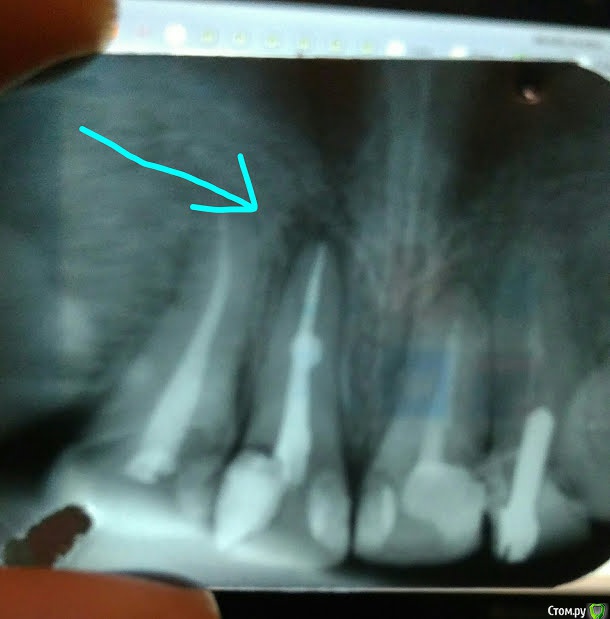

ya2mama Опубликовано 27 марта, 2018 Поделиться Опубликовано 27 марта, 2018 Беспокоит слабовыраженная боль при надавливании на зуб и/или участка десны над ним, под самым носом. Зуб кариозный, сейчас лечу его. Стоматолог уже делал чистку канала (внутри был гной), вкладывал какое-то лекарство. Но болезненность не проходит... Начала сомневаться в профессионализме лечащего врача... Снимок прилагаю. Сделан уже после "лечения". Подскажите, что на нем? И как с этим бороться? Сейчас канал запломбирован, на самом зубе установлена временная пломба. Ссылка на комментарий

St. Опубликовано 27 марта, 2018 Поделиться Опубликовано 27 марта, 2018 По снимку канал в зубе запломбирован адекватно, после лечения такого хронического воспаления как у Вас может какое-то время быть дискомфорт. Он со временем проходит. Снимок прилагаю. Сделан уже после "лечения". Что сподвигло сомневаться в своем докторе? Ссылка на комментарий

St. Опубликовано 27 марта, 2018 Поделиться Опубликовано 27 марта, 2018 То темное что Вас смущает вокруг корня зуба проходит не за один месяц, а точнее минимум за полгода, бывает и дольше. Необходимости ждать я тоже не вижу. Закрывайте зуб постоянно, через 6 и 12 мес нужно будет сделать контрольные снимки 3 Ссылка на комментарий